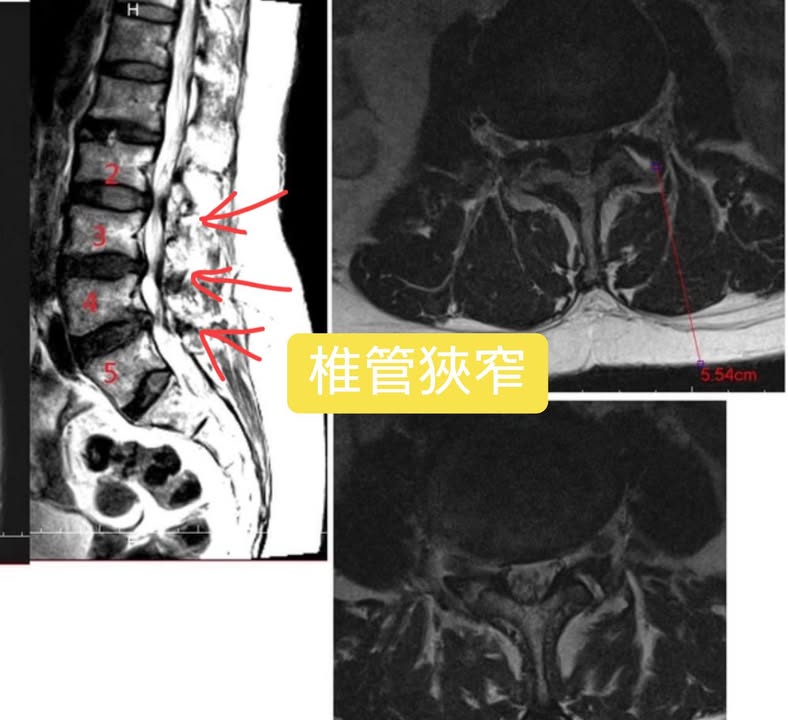

Cervical Spine Treatment Cases 腰椎治療案例 #巨大椎間盤突出醫案 #治療十二次提供前後MRI對比 #縱切面跟橫切面對比 #椎間盤突出為... 2021.09.03 ⭕️今天聽到患者說在某醫學中心開整段脊椎的刀 ,骨釘,骨水泥,人工椎間盤全上了,花... 2021.08.25 #典型下背手術失敗綜合症候群 #頸椎跟腰椎在短短幾年開了三次大刀 #腰椎融合固定支架... 2021.08.17 #馬尾神經症候群特殊醫案 #小便失禁合併下肢無力 #脊椎整合中醫微創逆轉勝 #脊刻救援... 2021.08.13 #骨刺髓核有可能吸收回去嗎?? #疼痛到無法行走的恐怖無法形容 #MRI核磁共振前後對比... 2021.08.14 #巨大椎間盤突出一定要開刀嗎? #兩家醫學中心外科醫師說很嚴重! #有沒有辦法逆轉勝... 2021.08.10 ❖ 椎間盤突出治療醫案 ❖晨起痛爆整個人無法工作心情沮喪 😂骨科醫師說復健如果沒效可... 2022.05.12 #天才年輕賽車手巨大椎間盤突出醫案 #八周治療完全逆轉勝康復 #重新回到合法賽車場競... 2021.07.20 #腰椎滑脫痛苦不堪 #右腳麻痛無法彎腰刷牙 #感謝桃園市楊小姐熱情見證 #患者親自贈送... 2021.06.15 #巨大椎間盤突出醫案 #真的逆轉勝超感動 #三個月治療完全徹底改善 #脊刻救援成功 #徹... 2021.06.12 ⭕️L4L5巨大椎間盤突出治療醫案 🌟八週之內解除危機逆轉成功 😁順利降級成功解封印 💪... 2021.07.08 #腰椎多節椎管狹窄治療醫案 #腎臟病患者可接受中醫微創筋膜療嗎? #感謝台北市信義區張... 2021.06.01 #腰椎手術失敗綜合症候群 #感謝桃園呂伯伯熱情見證 #何時必須優先考慮再次動刀 #脊刻... 2021.07.31 #感謝新店吳先生熱情見證 #車禍後導致椎間盤突出醫案 #傳統復健六周無效痛苦不堪 #脊... 2021.05.29 #椎間盤突出治療醫案 #破紀錄三週解決 #真的逆轉勝 #感謝新莊周先生熱情見證 #脊椎整... 2021.05.26 ← 上一頁 6 7 8 9 10 下一頁 →